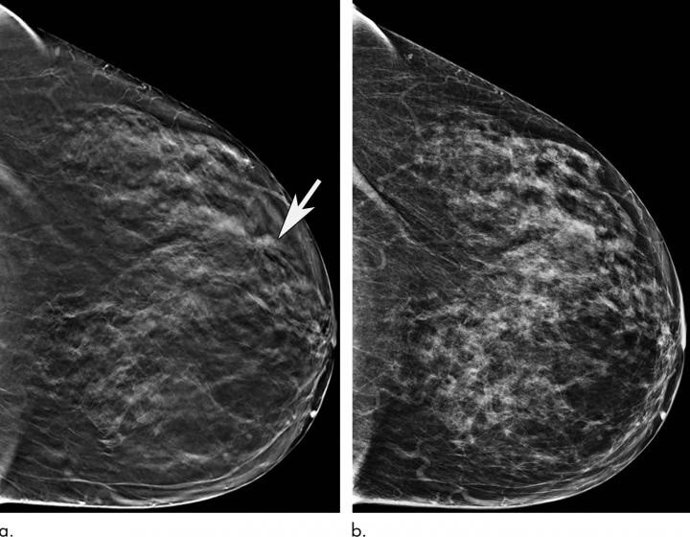

Archivo - Las mujeres mayores se benefician significativamente cuando se las examina con una mamografía 3-D

Archivo - Las mujeres mayores se benefician significativamente cuando se las examina con una mamografía 3-D - RADIOLOGICAL SOCIETY OF NORTH AMERICA - Archivo